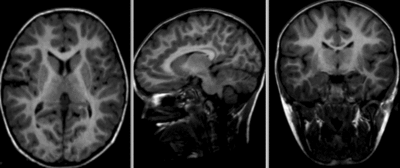

unregistered

original unregistered

rigid

affine

affine registered nonrigid registered (5,5,5 BSpline unmasked)